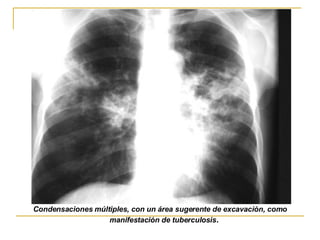

Condensaciones múltiples, con un área sugerente de excavación, como manifestación de tuberculosis .

Condensaciones múltiples, conun área sugerente de excavación, como manifestación de tuberculosis .